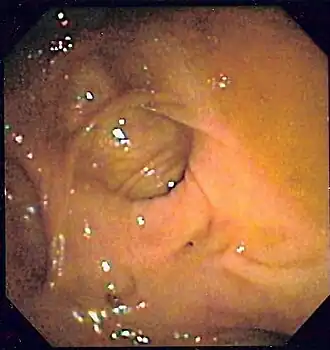

Colonoscopia

Es el método diagnóstico inicial más indicado para la mayor parte de los pacientes.[95][107]​ Consigue el diagnóstico entre el 75 y el 100% de los casos (con un 91% de media).[108]​ Y además ofrece la posibilidad de hacer tratamiento de la lesión. La potencia diagnóstica de la colonoscopia es mayor que la del resto de métodos diagnósticos radiológicos, ya que estos requieren que haya sangrado activo en el momento del examen.[17][4]

Para determinar la certeza de haber encontrado la localización o lesión de la hemorragia se aplican una serie de criterios diagnósticos endoscópicos, que están basados en los utilizados en la endoscopia de la HDA. Estos criterios vienen descritos en la tabla 4.

Tabla 4. Criterios diagnósticos endoscópicos de localización de la hemorragia en el colon (Zuckerman y Prakash 1998,[6]​ Green et al. 2005[113])

Grado de probabilidad Tipo Criterio

Definitivo 1 Lesión con hemorragia activa: visualización de emanación activa de sangre de un lugar específico o de una lesión fácilmente identificable, hemorragia que persiste a pesar de haber irrigado profusamente la zona.

Definitivo 2 Lesión no hemorrágica con vaso expuesto visible: lesión muy localizada protuberante de coloración púrpura o roja.

Definitivo 3 Lesión con coágulo adherido: coágulo denso y adherido que persiste a pesar de lavado profuso del mismo.

Presuntivo 4 Sangre reciente localizada en un segmento determinado del colon situado en la misma localización que una lesión potencialmente sangrante o distal a dicha lesión.

Presuntivo 5 Divertículo ulcerado con sangre reciente en una zona próxima.

Probable 6 Ausencia de sangre reciente en íleon terminal con sangre presente en el colon.

Como un alto porcentaje de hemorragias bajas ceden espontáneamente, hay muchos diagnósticos endoscópicos dudosos cuando no se identifica una lesión hemorrágica activa o un coágulo adherido evidentes. Es frecuente, por ejemplo, que se vean varios divérticulos y además una angiodisplasia, o unas hemorroides internas congestivas, sin signos de sangrado ni coágulo adherido en ninguna de estas lesiones. En ocasiones, será la presencia de sangre en un nivel u otro del colon junto con las lesiones potencialmente sangrantes lo que nos determine la impresión diagnóstica.[7]